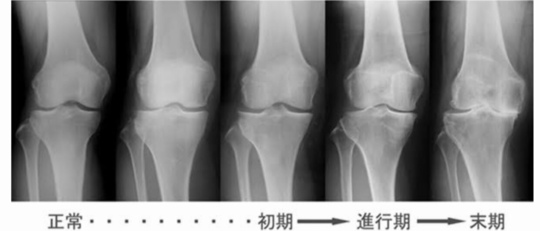

変形性膝関節症の進行度合い

変形性膝関節症の初期は50代からはじまり、歳を重ねていくごとに変形は進行していきます。

痛みを繰り返すから骨はどんどん変形していき、最終的には末期の変形になります。

痛みを繰り返すと『炎症』を何回も繰り返すことになり膝関節の可動域がどんどん狭くなっていきます。